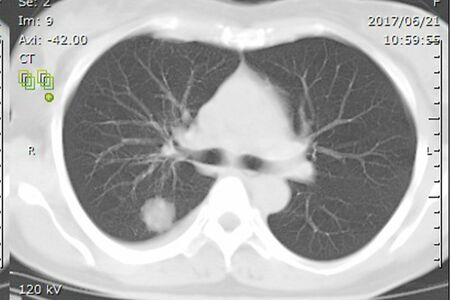

松本みゆきさんが見ても、すぐに「肺がんだ」とわかったというCT画像。白い影がはっきりと写り込む

[写真 2/5枚目] 松本みゆきさんが見ても、すぐに「肺がんだ」とわかったというCT画像。白い影がはっきりと写り込む